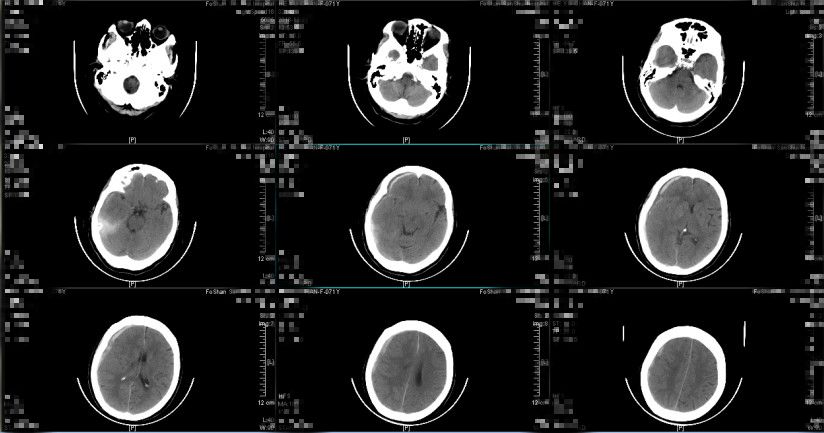

患者于2019年1月3日早上8点左右出现意识障碍,神志模糊,GCS评分10分,考虑硬膜下血肿继续增多、颅压高引起,予20%甘露醇250ml 快速静滴并同时送至CT室复查头颅CT提示(图7、图8):亚急性硬膜下血肿继续较前增多,最大厚度约2cm,中线向左偏移大于1cm,环池受压,有明确的手术指征。经脱水药物处理后,患者神志转清,GCS评分上升到14分,再次与患者及其家属讲解病情及治疗方案,选择予微创手术治疗方案。遂于当天早上9点左右行右额部微创针穿刺亚急性硬膜下血肿引流术,术中予生理盐水反复置换冲洗,术后行定时开放、夹闭引流,行阶梯性减压,利用脑复张促进血肿引流。

图7.(2019-01-03 08:34:45)

图8

留置头部微创针引流管引流1天,引流量约200ml,患者神志清,头痛等症状减轻,复查头颅CT提示亚急性硬膜下血肿大部分消除,最大厚度约0.2cm,中线大致居中,环池清晰,手术效果明显,予拔除微创针引流管,继续与立普妥药物治疗。

图9. 术后24小时复查头颅CT提示:亚急性硬膜下血肿大部分消除,中线大致居中,环池清晰。(2019-01-04 10:01:05)